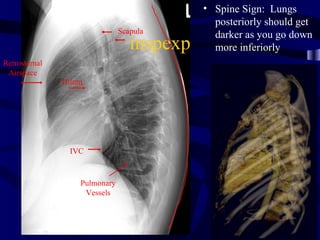

• Spine Sign: Lungs

Scapula

darker as you go down

inspexp     more inferiorly

Retrosternal

Airspace

Hilum

IVC

Pulmonary

Vessels